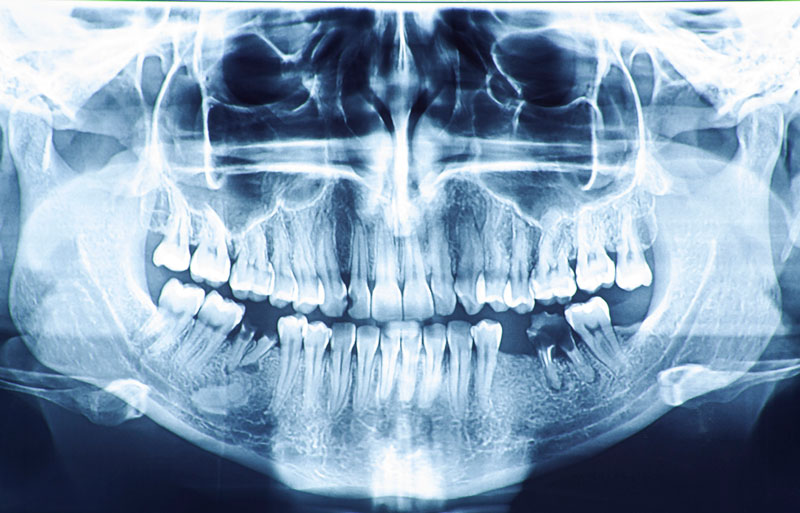

a. Chụp phim X-quang hoặc CT Cone Beam

- Giúp bác sĩ đánh giá mật độ, thể tích và tình trạng xương hàm.

- Xác định vị trí dây thần kinh, xoang hàm để tránh tổn thương trong quá trình cấy ghép.

- Chụp X-quang hoặc CT Cone Beam để đánh giá tình trạng xương hàm.